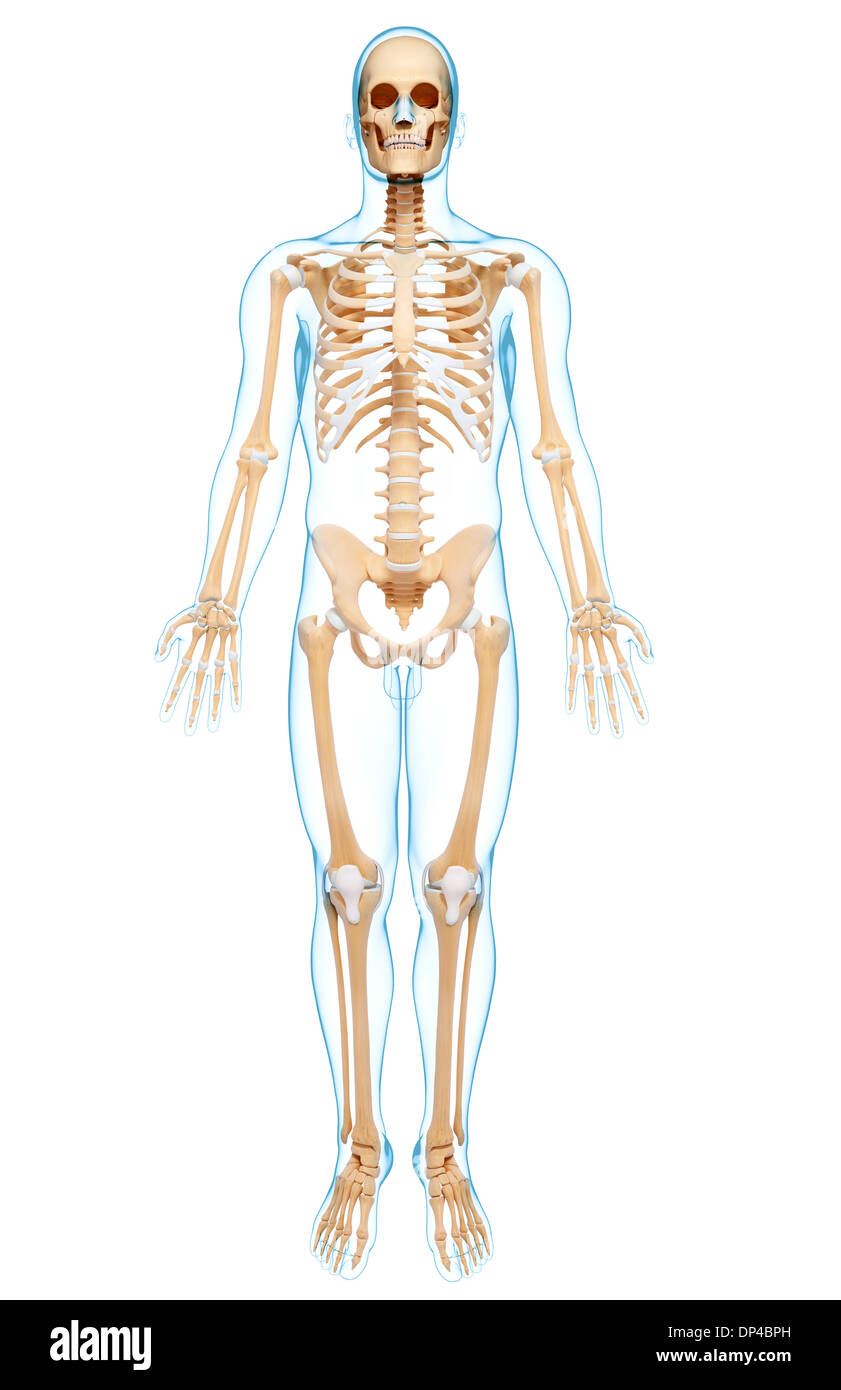

Human Skeleton, artwork Banque D'Imageshttps://www.alamyimages.fr/image-license-details/?v=1https://www.alamyimages.fr/human-skeleton-artwork-image65250601.html

Human Skeleton, artwork Banque D'Imageshttps://www.alamyimages.fr/image-license-details/?v=1https://www.alamyimages.fr/human-skeleton-artwork-image65250601.htmlRFDP4BPH–Human Skeleton, artwork